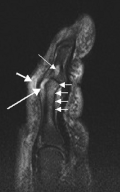

Severe psoriatic arthritis of both feet and ankles. There is also damage to the nails.